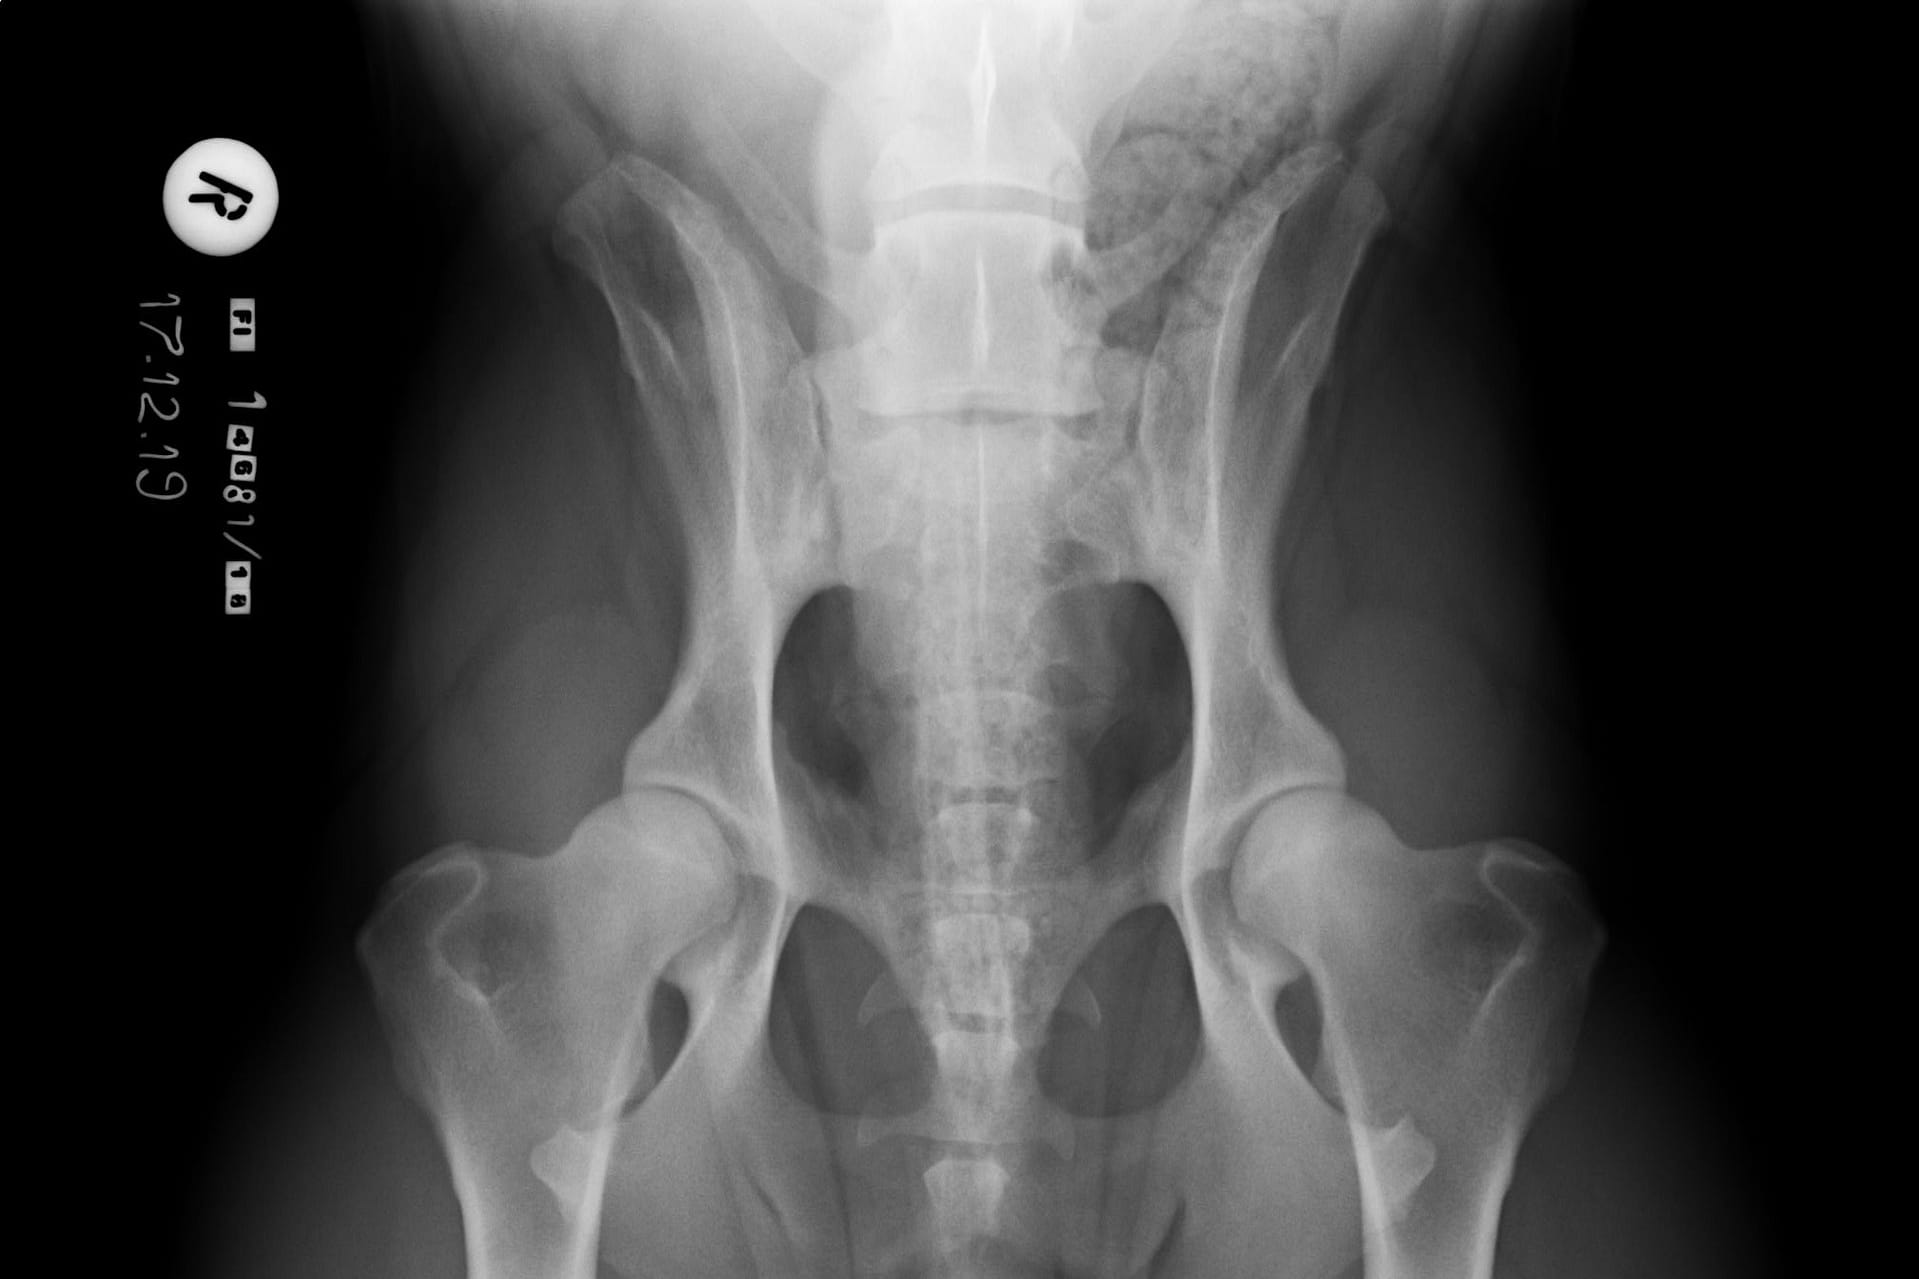

LTV3, epäsymmetrinen lanne-ristinikama näyttää olevan muita muotoja harmillisempi. Joissain tapauksissa epäsymmetriseen lanne-ristinikamaan liittyy vino lantio, joka saattaa aiheuttaa myös lonkkien epätasaista kehitystä. Tämä on varsin loogista; kun lantio on vino kohdistuu paine lonkkamaljoille epätasaisesti. Pidemmän ajan kuluessa epätasapaino voi kuluttaa toista lonkkamaljaa nopeammin ja aiheuttaa tätä kautta nivelrikkoa.

KoiraNetin mukaan 38,9% LTV3-lausunnon saaneista rhodesiankoirista on saanut lonkkien osalta lausunnon, jossa toinen lonkka on 1-2 astetta toista huonompi, esimerkiksi A/C (lokakuu 2020). Tutkimustulos LTV3 ei kerro koiran lantion asentoa.

”Asymmetrical LTV favours pelvic rotation over its long axis, resulting in inadequate femoral head coverage by the acetabulum on one side. Inadequate coverage of the femoral head favours subluxation, malformation of the hip joint, and secondary osteoarthritis. Asymmetrical hip conformation may therefore be the sequela of a LTV and mask or aggravate genetically induced canine hip dysplasia.”

(Flückiger M., Frank Steffen F. et al 2017)